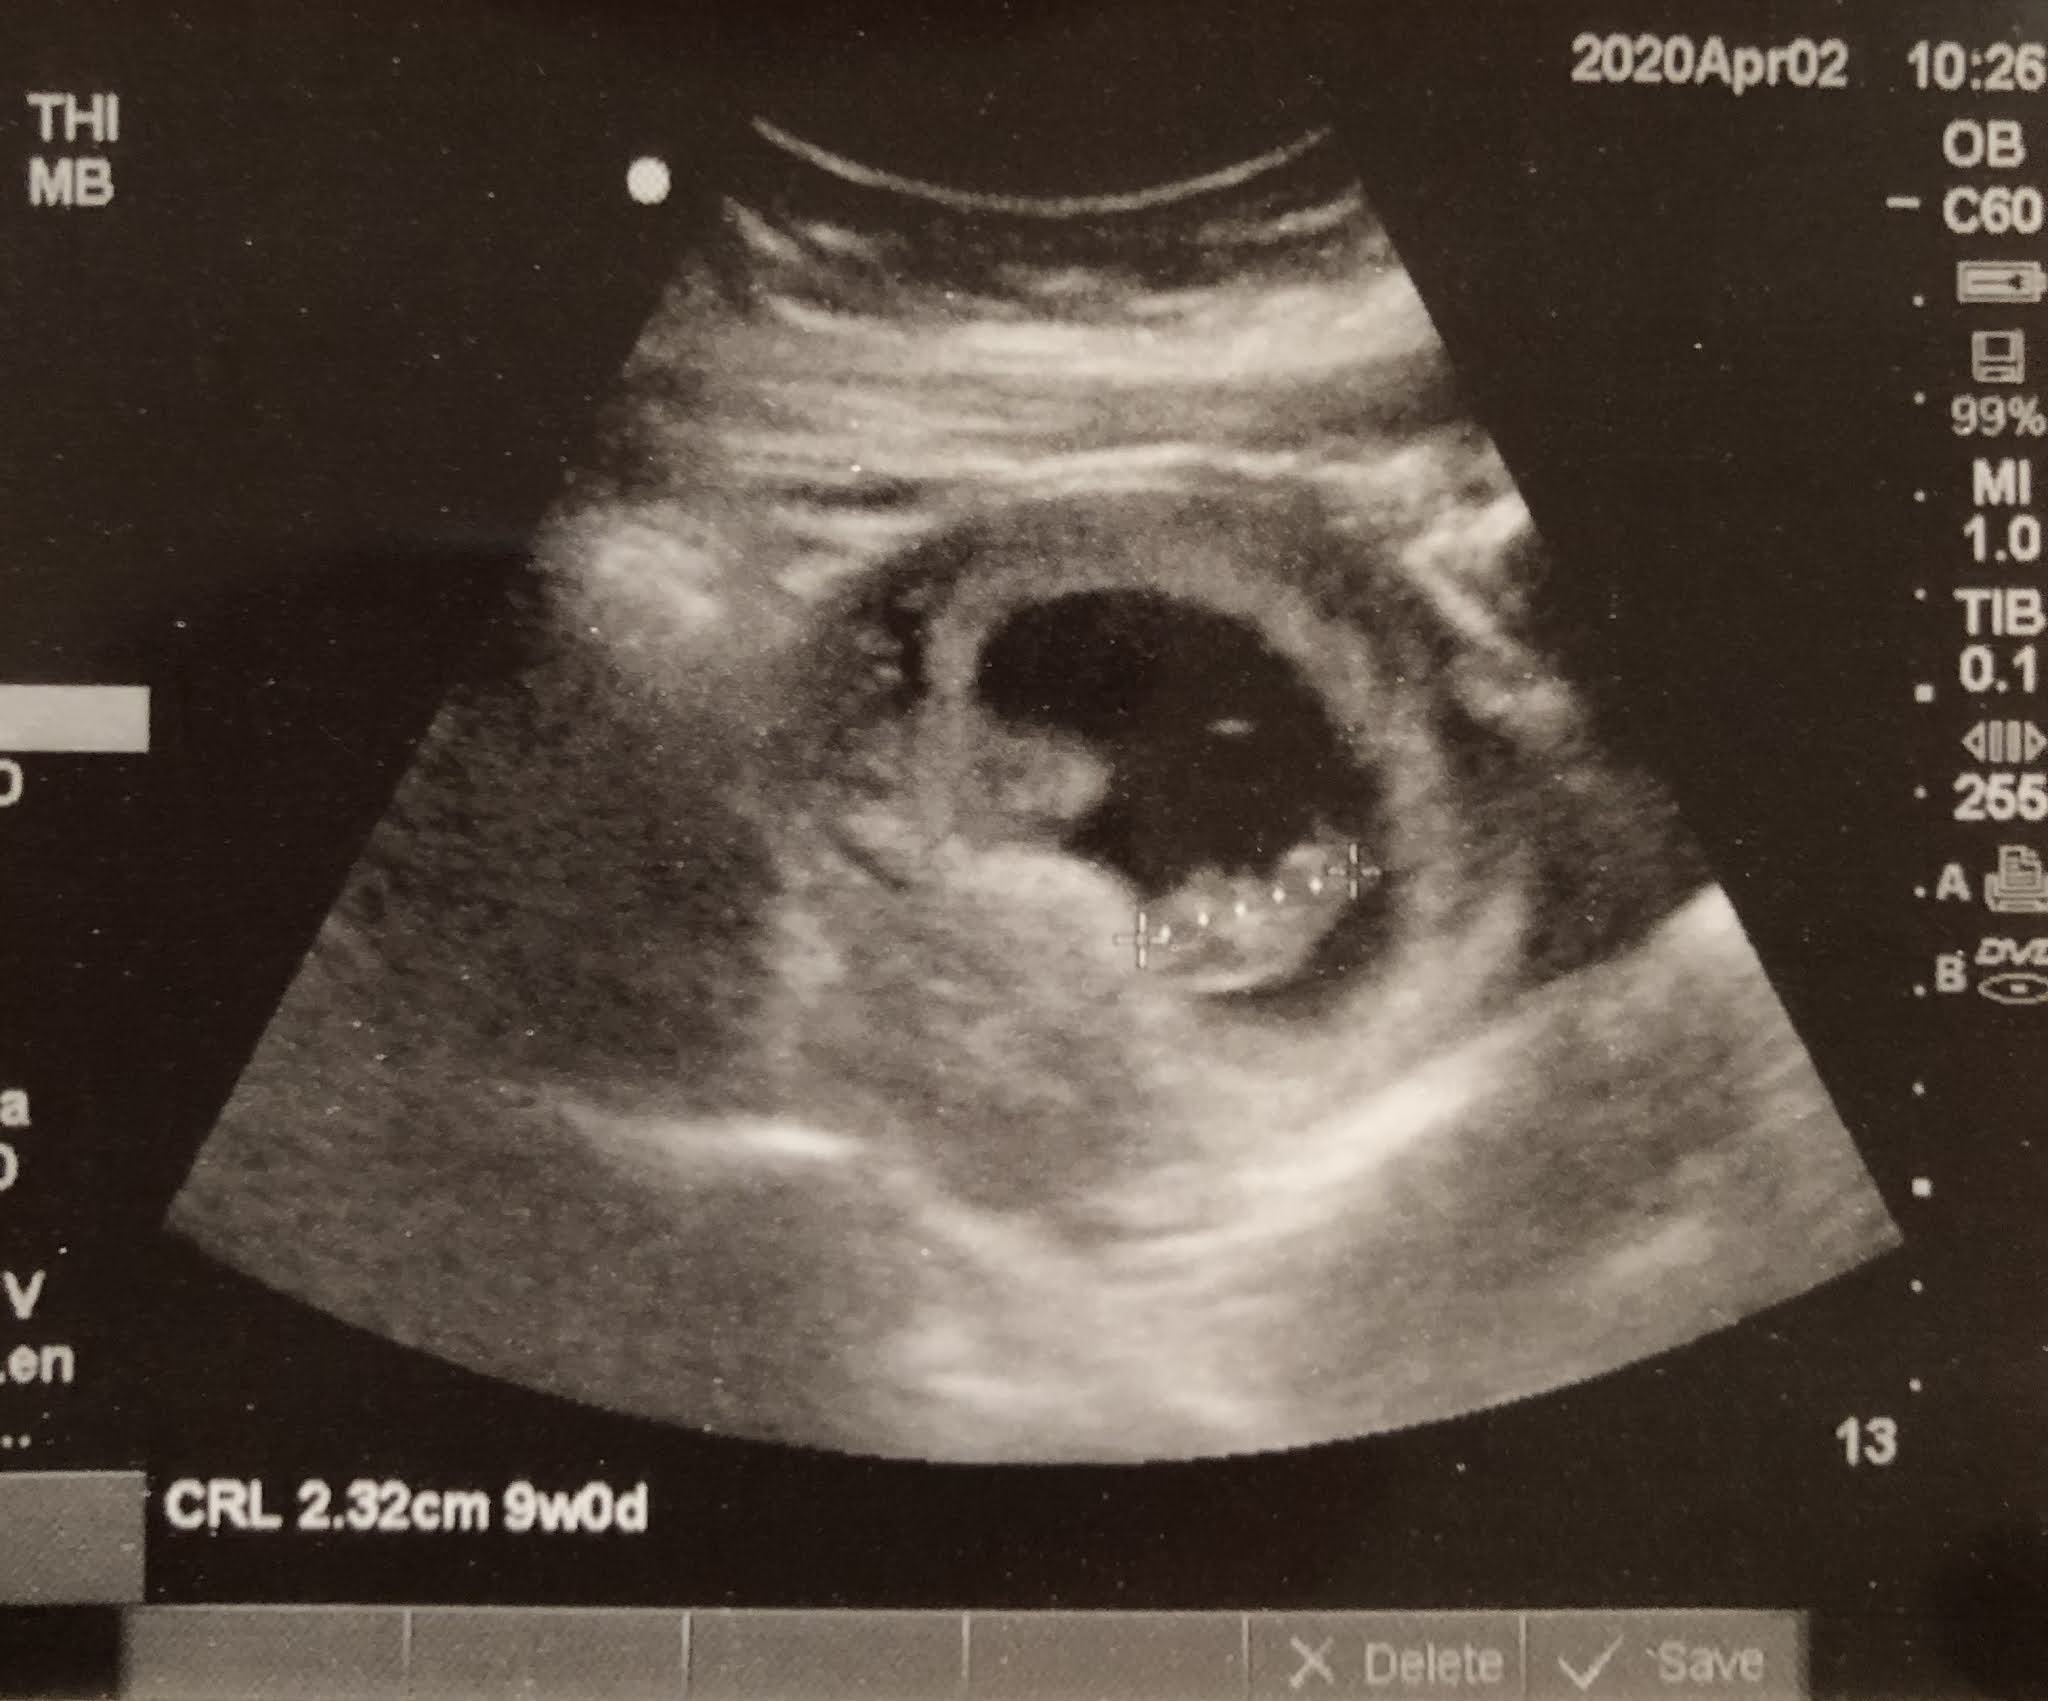

The Monday after we told our parents the news, I had my first appointment at the San Francisco Birth Center where we got our first peek inside my uterus and saw that tiny heart beating away. It was beautiful!